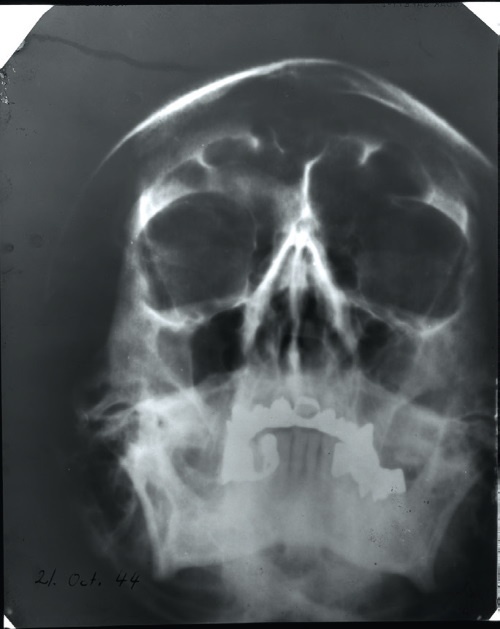

![]() Два главных экспоната из дела Гитлера, хранящиеся в ГА РФ (Государственный архив Российской Федерации) в Москве. По словам хранителей, это фрагменты дивана, на котором фюрер совершил самоубийство, в коробке из-под компьютерных дисков – фрагмент черепа Гитлера. ![]() Фрагмент черепной коробки, хранящийся в ГА РФ в Москве. Сообщается, что он был обнаружен перед запасным выходом фюрербункера в Берлине в мае 1946 года во время дополнительного следствия, проведенного советскими следователями по делу Гитлера. Видны пулевое отверстие, следы, оставленные огнем, и крошки земли. ![]() Фрагменты челюсти Гитлера. Советские следователи изъяли их из трупа, обнаруженного 4 мая 1945 года в саду новой рейхсканцелярии в Берлине. В настоящее время они хранятся в архивах российской секретной службы, в ЦА ФСБ. ![]() Фрагмент обгорелой челюсти Гитлера с зубами. Следы, оставленные огнем, свидетельствуют о том, что он был сильным, но не долгим, почему зубы и протезы почти не повреждены. ![]() а) ![]() б) Голубоватые пятна, которые присутствуют только на одной стороне челюсти. Их можно видеть справа на фото а). Пятна ярко-голубого цвета (снято с увеличением под микроскопом на фото б). Что это, следы цианида? К концу жизни у Гитлера было только четыре здоровых зуба без коронок. Чтобы спасти один из них, он и попросил своего дантиста сделать этот протез в форме желобка. Его уникальная и узнаваемая форма облегчает работу по идентификации фюрера. ![]() Рентгеновский снимок лица Гитлера, сделанный осенью 1944 года (в настоящее время хранится в Национальном архиве, Колледж-Парк, Мэриленд, США, № 27500765). Металлические зубные протезы видны на нем в виде белых пятен. В частности, тот, который был изготовлен в виде желобка, слева, внизу. ![]() Фотографии, сделанные советскими следователями в мае 1946 года в фюрербункере в Берлине. Предположительно это диван, на котором Гитлер совершил самоубийство. На правой стороне подлокотника – темные пятна. Это кровь диктатора? ![]() Детали фрагментов дивана, хранящиеся в ГА РФ в Москве. Следы темных потеков (рядом с куском ткани) еще видны спустя семьдесят лет после события. |